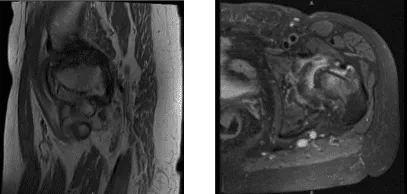

MRI Left thigh non-contrast

An MRI was reviewed and discussed by the doctor; Left Thigh MRI, the Bones T1 marrow signal intensity is maintained within without evidence for aggressive osseous lesion or osteonecrosis. No acute fracture is present. There is no marrow or periosseous edema.

Please note that this study was not tailored to evaluate for internal derangement of the Joints. Nevertheless, no significant joint effusions are present. There is an oblique tear in the posterior horn of the medial meniscus. The Muscles/Tendons has no full-thickness tendon tear or tenosynovitis is appreciated.

There is no disproportionate muscle atrophy. No acute muscle tear or denervation-related edema is present. There is no peri muscular fluid. The neurovascular structures demonstrate normal course.

The subcutaneous tissues are within normal limits. Oblique tear in the posterior horn of the medial meniscus. No fractures. No muscle tear or muscle edema in the thigh.